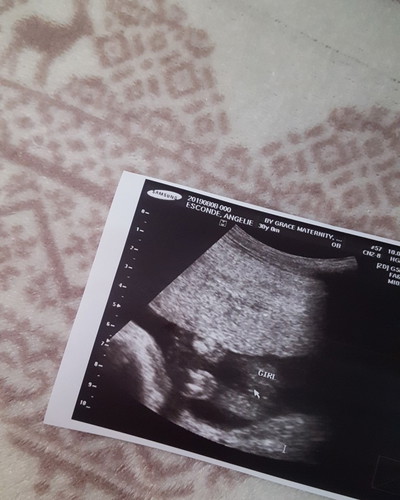

Congrats sis I feel youπsame tayo answered prayer din kami last pregnancy na to buti na lng baby girl na,3 boys na ksi silaπ. #28weeks

24 weeks sis nagpa ultrasound ako nung 22 weeks kaya lang ndi nagpakita gender si baby nakaharang daw cord nag crossed legs pa hehe...thanks sis :)

Congrats po. π samin po 3boys and baby girl sa tummy ko. π